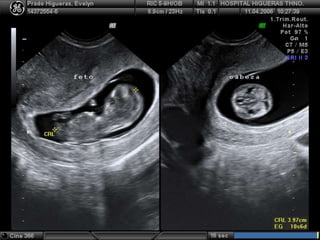

Ecografía obstetrica

 Debe verse siempre que DSM alcance los 16 a 18 mm

 Medición de la CRL es el mejor parámetro para estimar edad

gestacional

 Edad gestacional:

 42 + LEM en mm = Dias

 6,5 + LEM en cm = Semana

Rango de error +/- 5 dias